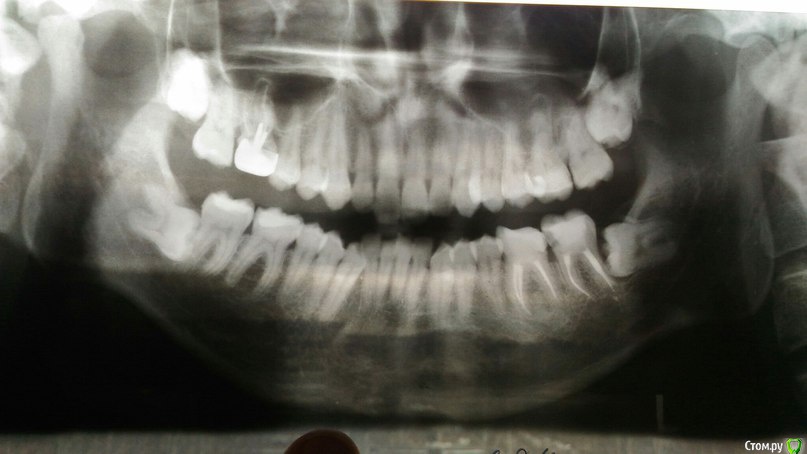

Дмитрий1990 Опубликовано 25 марта, 2016 Поделиться Опубликовано 25 марта, 2016 Здравствуйте! Сегодня нашел шишку у себя на десне над верхним зубом, сходил к врачу... она сказала что дело плохо, зуб надо удалять... отправила к другому врачу, что бы решил как лучше его удалить, но к нему я пойду только завтра. Там как я понял у меня загноились три корня и так просто его не удалишь могут быть последствия. Подскажите что лучше сделать и какие могут быть последствия. Благодарю! Ссылка на комментарий

___49___ Опубликовано 26 марта, 2016 Поделиться Опубликовано 26 марта, 2016 И 8ки удалите . Ссылка на комментарий